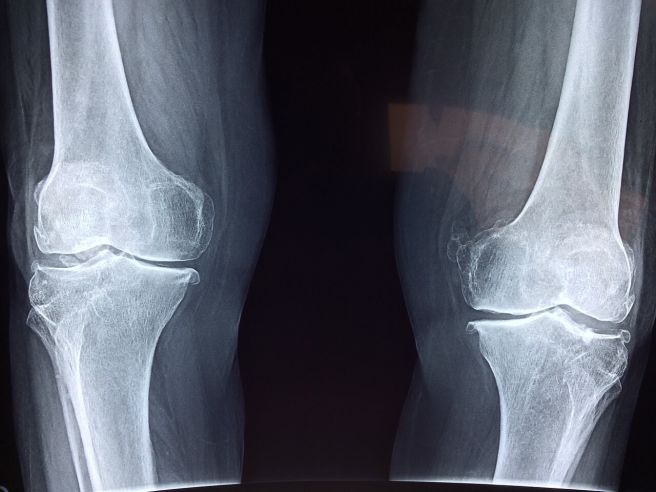

관절통과 근육통

주사 투여 후 관절과 근육 부위에 통증을 느끼는 사례가 보고되고 있습니다. 이는 약물이 뼈 대사에 영향을 주는 과정에서 염증 반응이 일시적으로 증가하기 때문으로 알려져 있습니다.

팔, 다리, 허리 등 여러 부위에서 쑤시거나 당기는 느낌이 나타날 수 있으며, 움직일 때 통증이 더 뚜렷해지기도 합니다. 근육이 뻣뻣해지는 느낌과 함께 힘이 빠지는 듯한 증상이 동반되는 경우도 있습니다. 관절 부위가 붓거나 열감이 느껴지는 사례도 있으며, 평소 관절 질환이 있는 분들은 통증 강도가 더 크게 느껴질 수 있습니다.